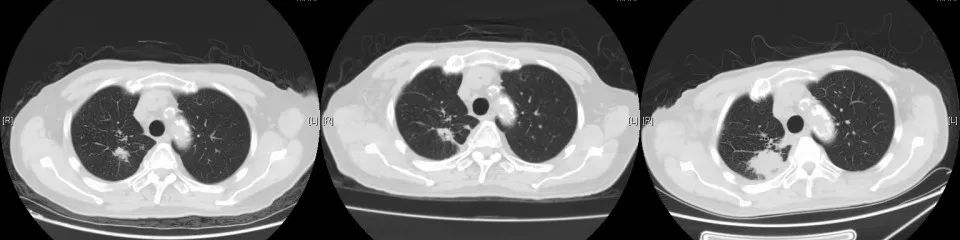

CT变化:

2018年1月复查胸部CT:右肺占位较前增大,余无明显特殊不适。外院再次行肺穿刺活检,病理:右肺组织见癌转移(符合膀胱癌肺转移)。2018年3月14-29日于我院行肺转移灶局部放疗。2018年5月15日-7月11日予标准方案化疗2周期。期间病情稳定。2018年10月复查,局部肺转移灶增大进展、且出现肺新转移灶,评估疗效PD,行NGS全基因检测,根据检测结果,即选用阿法替尼口服行靶向治疗。

2020年3月复查,病灶再次进展,参考前次基因检测结果,结合临床情况,即开始给予口服吡咯替尼80mg每日一次,2020年4月25因心梗住院治疗。停药约2周。复查示原转移灶稍增大,考虑是否与停药有关,故继续维持吡咯替尼治疗。期间多次复查,病情稳定。局部考虑缓慢进展可能。但综合考虑临床情况,仍继续维持原方案治疗。

2021年5月19日常规复查CT考虑多发肝转移,肺原局部病灶稍进展。考虑吡咯替尼耐药,即予停用。即予“替雷利珠”200mg行免疫治疗1次。无明显副反应。2021年6月因肺部感染、合并心衰去世。